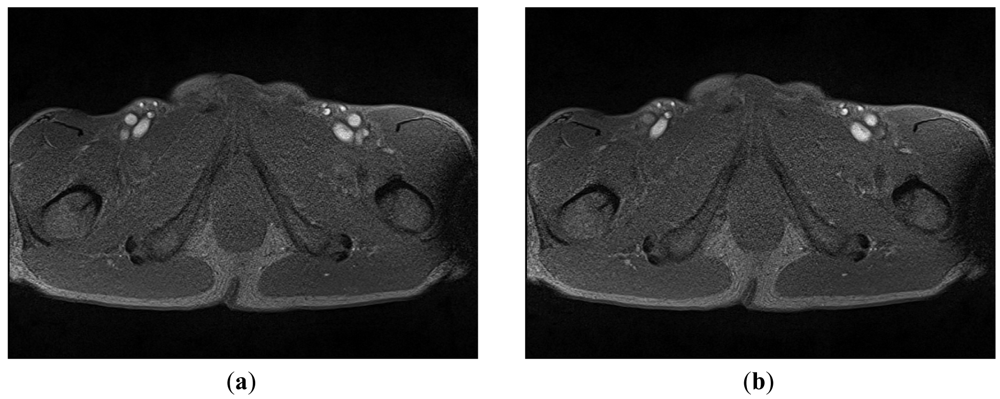

A mobile 1.5-T Magnetom (Siemens-Avanto™, Model Mob. MRI 02.05, Siemens Ltd., Erlangen, Germany), with a flexible 6-channel body matrix coil with 6 integrated low-noise preamplifiers (Siemens Ltd.) and bilateral table fixation, was used to acquire SFA MRI sequences from the subjects. All of the participants were athletes. The athletes were fixed in a stretched supine position, head forward on the MR table. To identify the axial perpendicular acquisition location at the right SFA 10 mm beneath the bifurcation of the common femoral artery, a biplane coronal and sagittal localizer (TRUFI: “true fast imaging with steady state precision”; Siemens Ltd.) was used. As in the common carotid artery MR-measurement, changes in the SFA diameter during systole and diastole was assessed with a T2*-weighted gradient-spoiled gradient-echo cine-sequence (FLASH: “fast low angle shot”, Siemens Ltd.) in a two-dimensional cross section view with prospective two-dimensional ECG gating (cardiac triggering). Specific sequence parameters were set thus: flip angle 15°, echo time variable between 4–6 ms (depending on heart rate), repetition time variable 20–40 ms (depending on heart rate), slice thickness 6 mm, field of view 768 cm2, matrix size 512 × 384, pixel width 0.625 mm (pixel area 0.3906 mm2) ISO, pixel bandwidth 250, and 50 images per sequence for one RR-cycle (approximately 300 heart beats per sequence). The total imaging acquisition time was approximately 4 min 30 s to 5 min for each sequence. Figure 3 shows two typical MRA images: 3(a) was taken in the systolic phase and 3(b) in the diastolic phase.